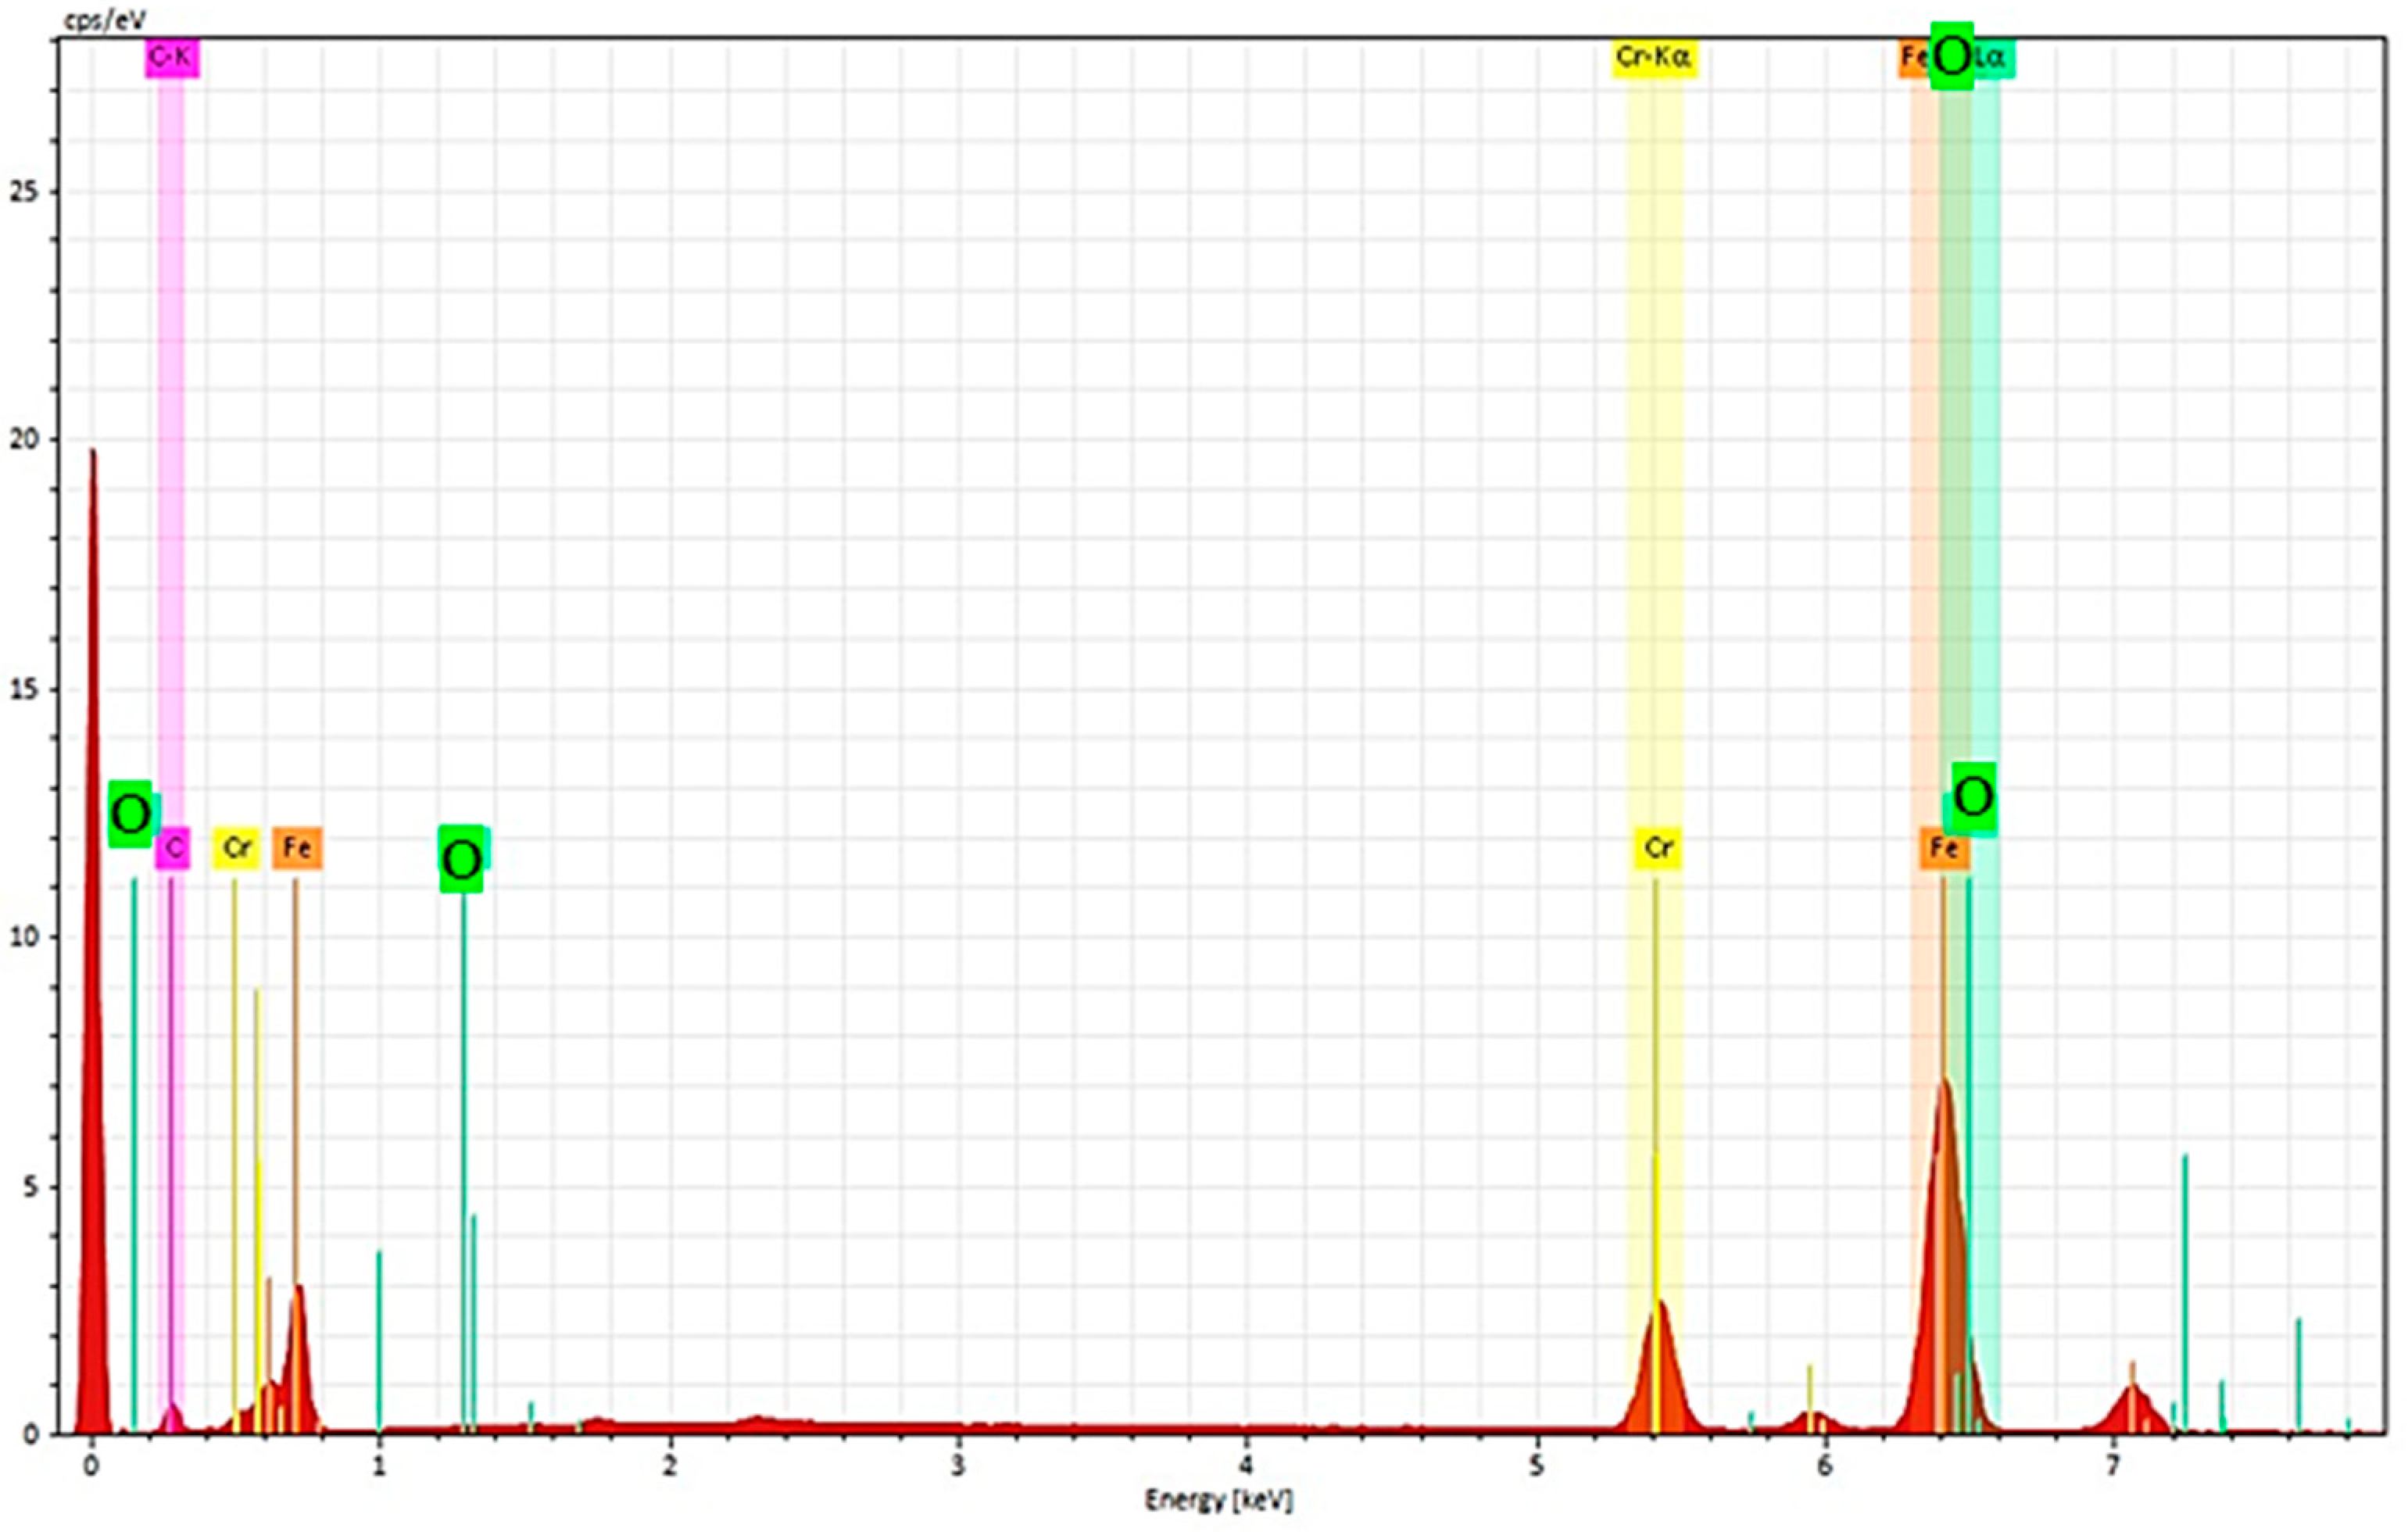

3.2. Scanning Electron Microscopy-EDS Analysis

3.2.1. Non-Sterilized Drill and Conical Tapper

3.2.2. Used and Sterilized Drill and Conical Tapper